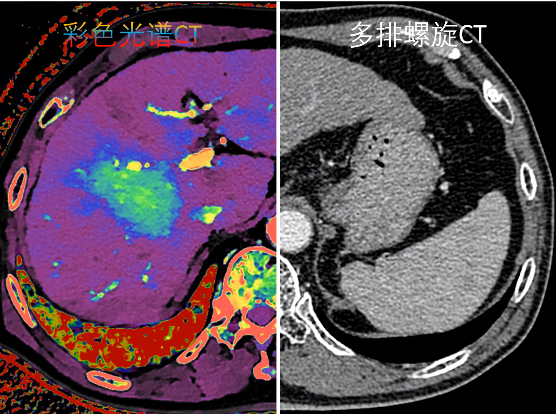

从黑白单参数到彩色多参数

彩色光谱CT2016年,全球首台基于双层探测器的光谱CT诞生,通过空间上对等的上、下两层探测器分别接收高、低能量的X线光子,实现探测器端的能量解析和彩色光谱成像。

自1971年CT诞生以来,经过50年的发展实现了从扫描速度慢、分辨率低的黑白成像逐渐发展到了扫描速度快和分辨率高的彩色成像。

总结:自1971年CT诞生以来,经过50年的发展实现了从扫描速度慢、分辨率低的黑白成像逐渐发展到了扫描速度快和分辨率高的彩色成像(如上图所示)。